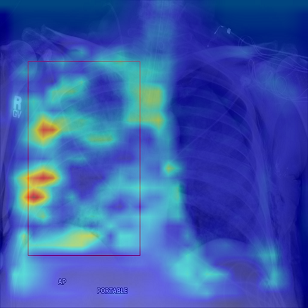

Refer to caption

(a) X-ray image with marked lesion

(b) The corresponding attention map

Figure 9: Visual results of attention map. We used Grad-CAM[41] to visualize the activation heatmap of the model. Note that by visualizing the heat map of attention, we can detect the lesion area indirectly, and help doctors to locate the lesion area for the better diagnosis.

As shown in Fig.7, we adopted ResNet18 as the backbone. We conducted ablation experiment, and added four techniques in the training process to observe the change trend of accuracy with the training time. It can be seen that the effect of training a single ResNet18 classifier without adding any techniques is worse than that of training with techniques, but the training costs less computation resources. In contrast, after adopting self-supervised contrastive learning strategy to pre-train the backbone, we found that not only the accuracy was improved, but also the convergence was much faster than that without contrastive learning pre-training. This is because after the self-supervised pre-training in the first stage, the feature extraction capability of backbone in the second stage is better than that of the backbone directly trained from scratch, so the accuracy is improved, and after the pre-training, the model converges faster during the re-training. The accuracy of the model is also improved after adding Mask-guided Hard Attention and Feature Learning with Contrastive Regulation (CR), because as shown in Fig.9, these two techniques guide and drive the network to pay more attention to the lesion regions, which contains more discriminative features. In terms of convergence speed, compared with that without Mask-guided Hard Attention and Feature Learning with CR, the network with these two techniques converges faster in the training process, because during the training, masks are used as the guidance to guide the correct training direction, and contrastive regulation is used as the constraint, which is equivalent to providing a positive pull force and a driving force for the training. All these factors accelerate the convergence speed of network training. After Class-Balanced (CB) Focal Loss was added, although the accuracy was greatly improved, the convergence speed became slower, because CB Focal Loss needs to estimate the effective number of samples during training, and then conduct the re-weighting scheme. Note that Mask-guided Hard Attention and Feature Learning with CR only costs computation resources during the training phase, and the MGACR module can be discarded when the model conducts forward inference, which aims to help the model be better trained, so it costs no computation burden during the testing and inference phases. In general, as shown in Table.I, these four techniques can improve accuracy very well, and the introduced extra computation burden is not too large. These four techniques have solved three common problems and challenges well in medical images and achieve promising performance.